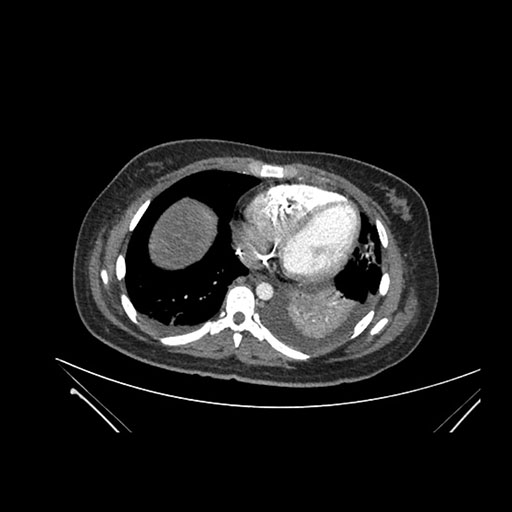

Imaging Analysis

Look through the patient's CT scan to identify any areas of concern for the necessary procedure.

Axial Arterial

Based on initial findings, which issue(s) would you be most concerned about?